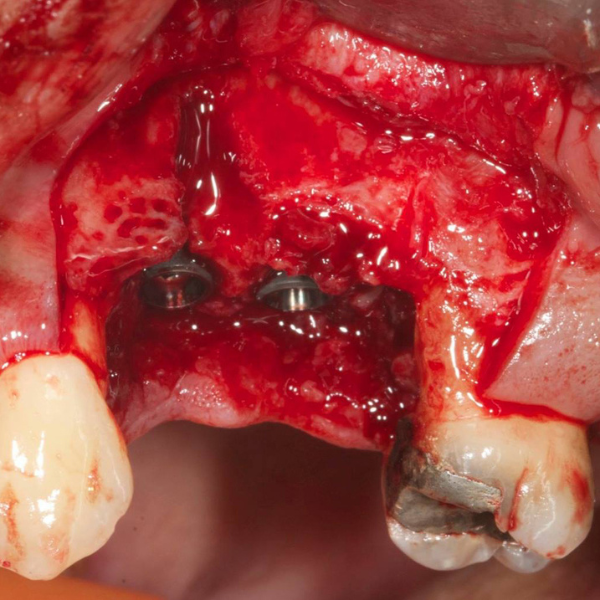

Tooth 14 slightly increased mobility, tenderness and bite pain. Suspected root fracture